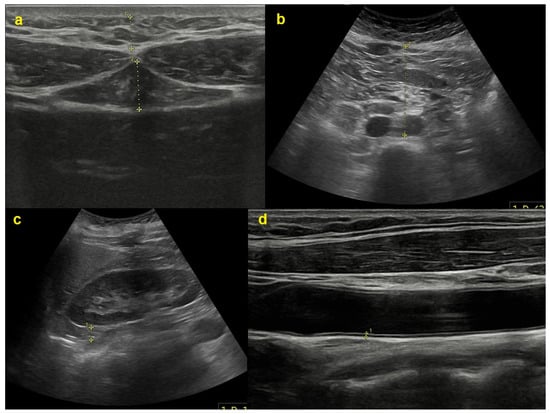

2.2. Imaging Procedures

- Hirooka, M.; Kumagi, T.; Kurose, K.; Nakanishi, S.; Michitaka, K.; Matsuura, B.; Horiike, N.; Onji, M. A technique for the measurement of visceral fat by ultrasonography: Comparison of measurements by ultrasonography and computed tomography. Intern. Med. 2005, 44, 794–799. [Google Scholar] [CrossRef] [PubMed]